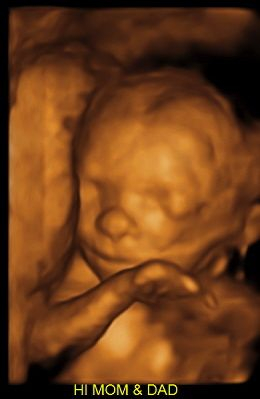

But in the meantime....LOOK AT THAT FACE!!! 😍

Baby girl's cute little face at exactly 28 weeks 😍